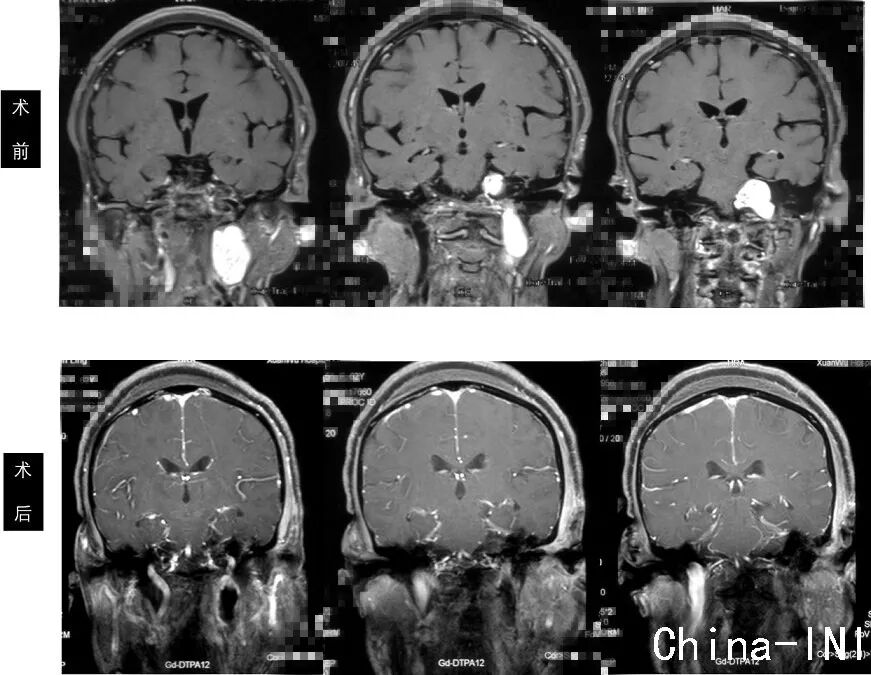

MRI轴位增强像示左侧颈静脉孔区神经鞘瘤,肿瘤呈哑铃型,同时侵及颅内、颈静脉孔及颈部,属于Samii颈静脉孔神经鞘瘤分型之D型,Fukushima分型之C型。

MRI冠状位增强像示肿瘤同时波及颅内、颈静脉孔及颈部,上端接近小脑幕水平,下端达第三颈椎水平。

MRI矢状位增强像示肿瘤呈哑铃型,从颅内经颈静脉孔,向颈部延伸到第三颈椎水平。

术后MRI复查,显示肿瘤切除彻底;

患者术后无新发颅神经症状,一周后拆线,伤口愈合良好,无皮下积液。